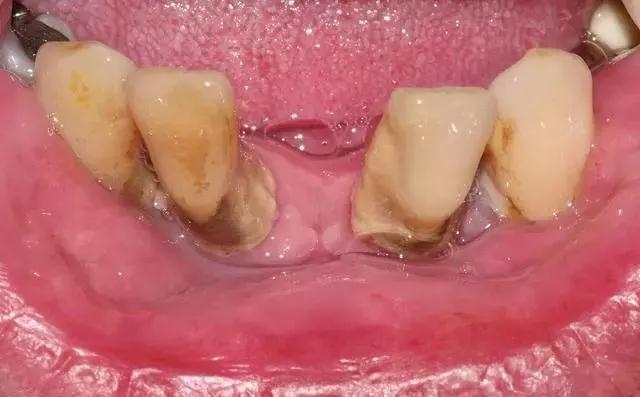

1、牙周病

牙周病在人群中普遍存在,它是牙齿松动的主要原因,因为各种原因导致了牙周膜长期受到慢性的炎性刺激,使得牙周膜纤维遭受到破坏。

这样牙周膜受到破坏就无法支撑住牙齿,导致了牙齿松动的出现。